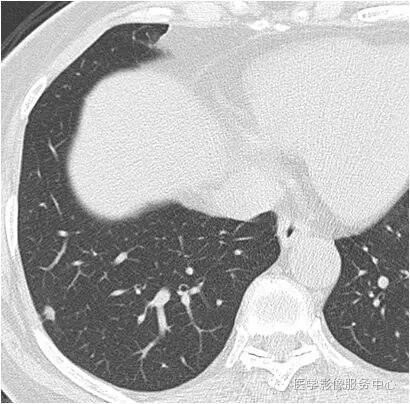

影像图片

结果:肺内淋巴结

黄勇主任解读:肺内淋巴结以老年人和吸烟者多见。

影像上常见于胸膜或叶间胸膜下,迄今为止,所有的报道均距胸膜或叶间胸膜小于2.0cm。也可以表现为与胸膜或叶间胸膜相贴的结节。绝大多数位于中下叶(气管隆突水平以下),上叶也可见到,但较少见。

长径均小于12mm。典型的形状为三角形,也可以为梭形、圆形或椭圆形。诊断的关键在于见到1-5条细线与胸膜、叶间胸膜相连,或注入肺静脉,但厚层CT显示欠佳。有作者病理对照线状影为小叶间隔,有作者病理对照为淋巴管。其实是统一的,因为淋巴管走行于小叶间隔内。

需要与小肺癌、肺转移瘤进行鉴别。肺内淋巴结除细线状影外,边缘清晰无分叶,无毛刺,是与肺癌鉴别的关键。有作者对9例胸膜下的小于1cm的肺转移瘤进行对照,后者均为圆形,且无线状影与胸膜或肺静脉相连。

对怀疑肺内淋巴结的病例,必须行薄层扫描,推荐1.5mm及以下层厚。因为在5mm层厚图像,肺内淋巴结可以由于部分容积效应表现为磨玻璃密度结节,而且对线状影及病变形状的显示也欠清晰。

诊断肺内淋巴结最关键指出在于薄层扫描见到细线状影与胸膜、叶间胸膜及肺静脉相连。